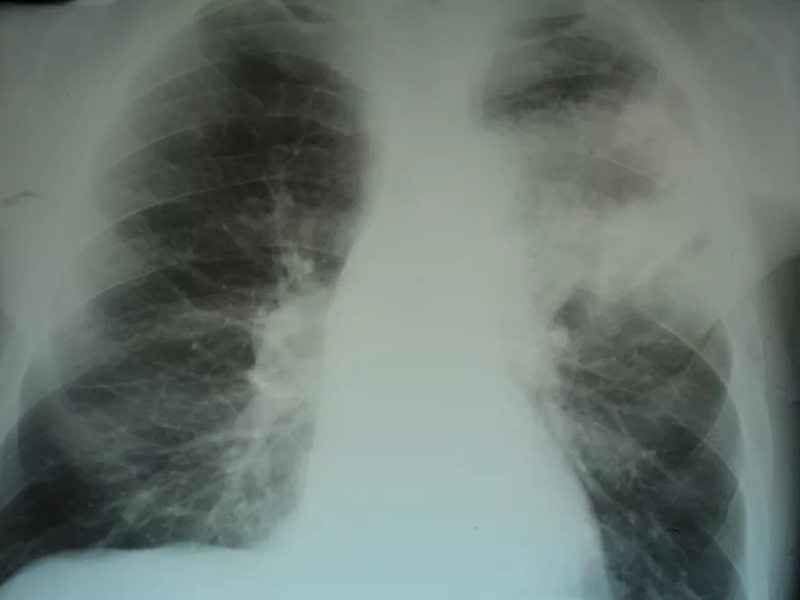

Крупозная пневмония на рентгене

При слиянии отдельных очагов воспаления легочной ткани возникает крупозная пневмония. Фото рентгеновского снимка, сделанного при этой форме заболевания, наглядно показывает отличия.

Как правило, при крупозной форме воспаления легких поражается одна или несколько долей легких сразу. Это создает серьезную угрозу жизни пациента.

На рентгене крупозная форма болезни проявляется следующими признаками:

- Ярко выраженные крупные тени, затрагивающие доли легкого целиком. Могут быть поражены оба легкого.

- Средостение смещается в сторону наиболее воспаленного легкого.

- На куполах диафрагмы отчетливо видны признаки деформации.

- Рисунок легочной ткани может не просматриваться.

Крупозная пневмония легче всего выявляется при рентгенологическом исследовании. Тем не менее для постановки точного диагноза врачи предпочитают делать рентгеновские снимки в двух проекциях. Это дает им возможность определить число пораженных воспалением сегментов органа и определить состояние средостения.